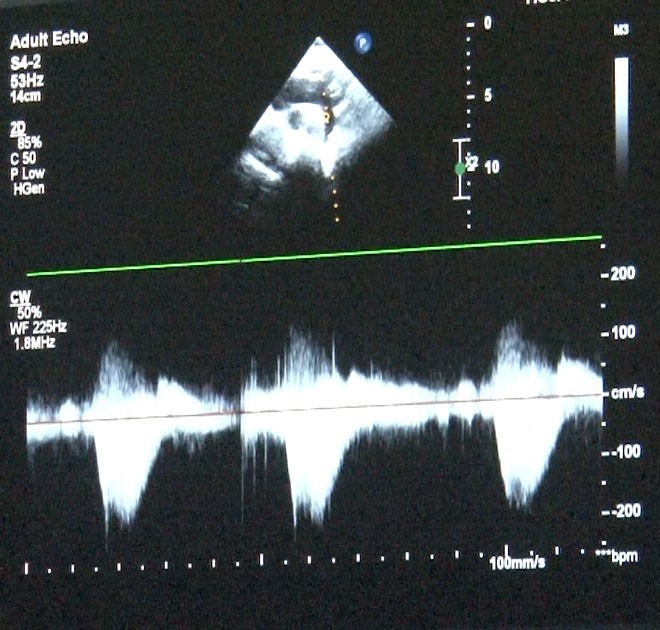

‘Sağlık Bakanlığı verilerine göre her yıl bin canlı doğumdan 8’inde doğumsal kalp hastalığı görebilmekteyiz’ diyerek sözlerine başlayan Uzm. Dr. Damla Gökçeer Akbulut, "Yılda 12 bin çocuk doğumsal kalp hastalığıyla dünyaya geliyor. Çeşitli nedenleri olabiliyor bazen annenin gebelikte kullandığı ilaçlar ya da diyabet gibi bir hastalığı olması, genetik rahatsızlıklar, bunlar genetik olarak kalp rahatsızlıklarına yol açabiliyor. Bu hastalarda erken tanı mümkün, daha anne karnındayken fetal ekokardiyografi (anne karnındaki bebeğin kalp yapısını ve işlevini değerlendirmek amacıyla kullanılan bir tıbbi görüntüleme)yle doğumsal kalp hastalığı olan bebeklerde doğum sonrası erken müdahale yapabiliyoruz. Bazı bebekler mor doğabiliyor ancak bazılarında bu bulgular ilk ay içinde gelişebiliyor" dedi.

Uzm. Dr. Gökçeer Akbulut ise, "Ailede daha önceden tanısı olmayan doğumsal kalp hastalığı olan bir bebek olduğunda hızlı nefes alıp verme, morarma ya da emerken soğuk terleme gibi bulgular varsa mutlaka çocuk hekimi kontrolünde bir çocuk kardiyoloğuna hızlıca yönlendirilmesi lazım. Doğar doğmaz müdahale edilmediğinde yaşamsal olabilecek sorunlarla karşılaşabiliyoruz, hasta kaybedilebiliyor. Anne karnında olmuyorsa da doğar doğmaz ekokardiyografi yaparak tanısını koymak mümkün. Hastalarda viral enfeksiyon ve kış döneminde RSV virüsü, ilk 2 yaştaki çocuklarda sık gördüğümüz bir viral enfeksiyon, sezonuna girmiş bulunmaktayız. Doğumsal kalp hastalığı olan çocuklarda ekim, mart ayları arasında mutlaka RSV aşılaması yapılmasını tavsiye ediyorum. İnfluenza dediğimiz belirtiler varsa ya da covid sonrası miyokardit dediğimiz kalp kası iltihabı görebiliyoruz. Çok ciddi boyutlarda şok tablosu dediğimiz tansiyon düşüklüğü, taşikardi dediğimiz nabız hızlanması ve solunum yetersizliği bulguları, hastada ödem artışı, hızlı nefes alıp verme gibi bulgularla yoğun bakım yatışı gerektirebiliyor. Kalp hastası olduğundan emin olduğumuz bir çocukta yıllık aşılamalarına influenza açısından devam edilmesini öneriyoruz" diye konuştu.